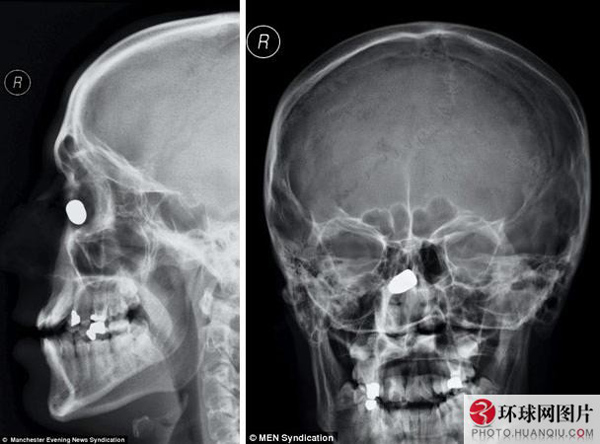

英国男子头部中枪后子弹卡在鼻骨幸存

21岁的英国人丹尼尔·格林伍德和朋友聚会时,突然遭遇入室抢劫,抢劫犯试图强行抢走丹尼尔脖子上戴的一条金项链。二人立即扭打在一起,在激烈反抗中丹尼尔被子弹射中头部。万幸的是,子弹竟然卡在了鼻骨处,丹尼尔捡回一条命。